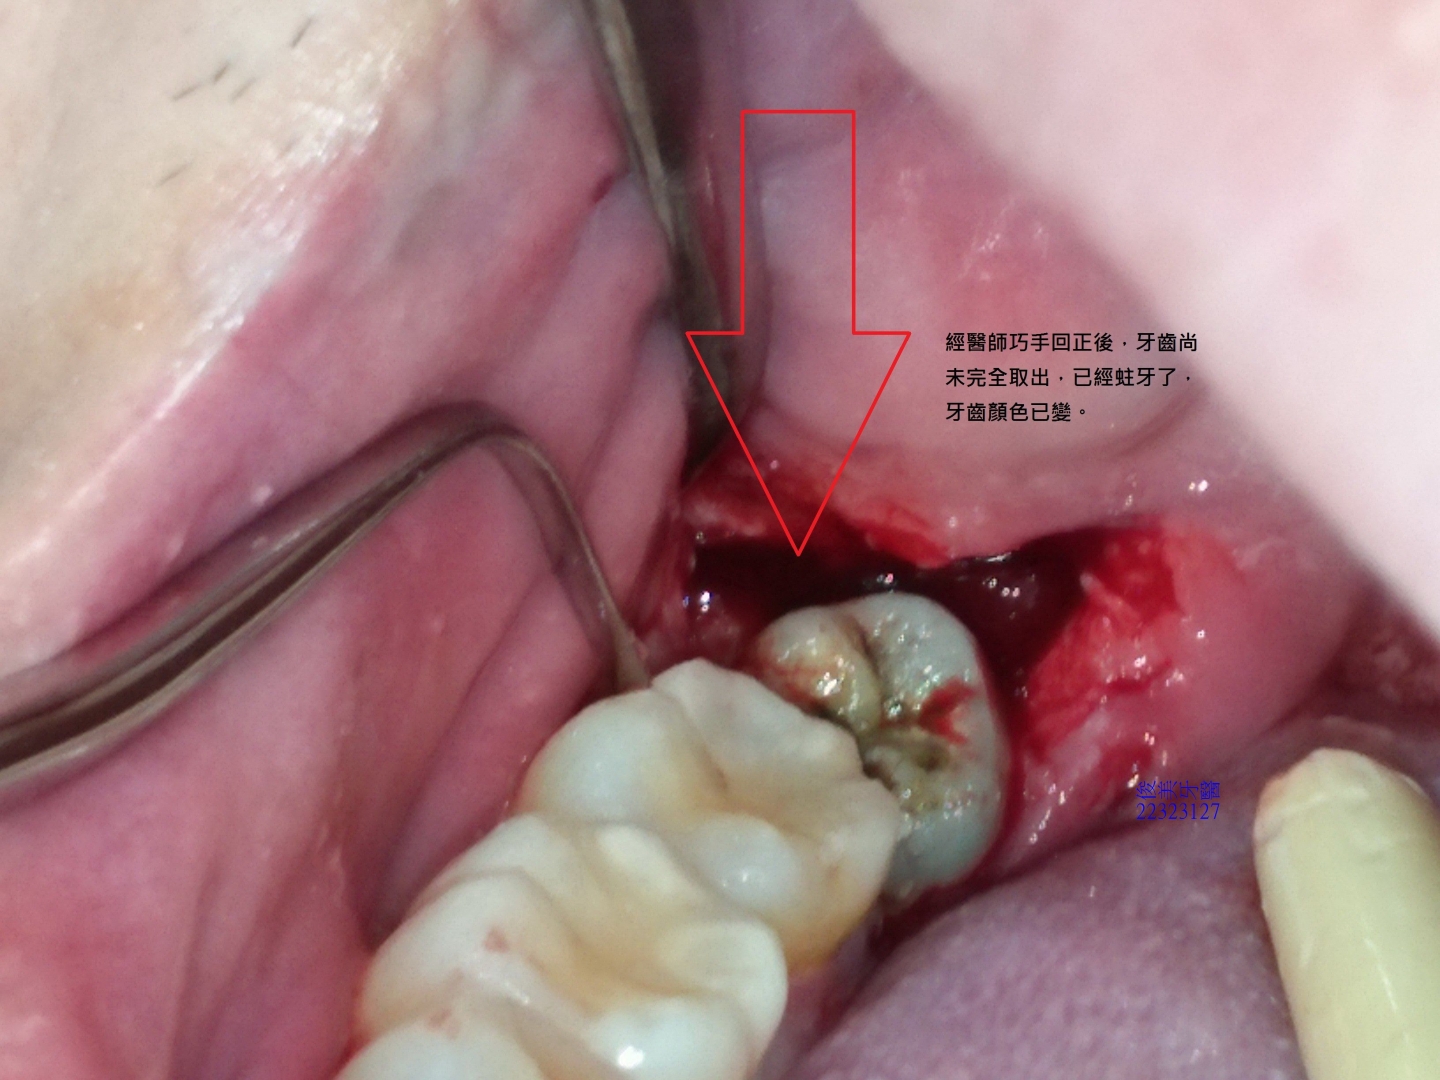

患者就診時表示,右下牙齒會痛,經醫師檢查後發現,患者因水平智齒未拔,導致塞東西且第二大臼齒蛀牙,因此建議患者在上藥消炎後,儘快將口內有副作用的智齒分次拔除。

患者在症狀緩解後,依次安排時間將口內智齒拔除。

並告訴醫師,之前的醫師跟他說:沒有痛,不用拔。

所以不知道後果這麼嚴重,還會讓好的牙齒蛀牙。

幸好遇到醫師會處理並告知正確的觀念,要將口內環境維持好清潔,少干擾,牙齒問題才會少,留著有副作用的牙齒,真的是給自已找麻煩,得不償失。